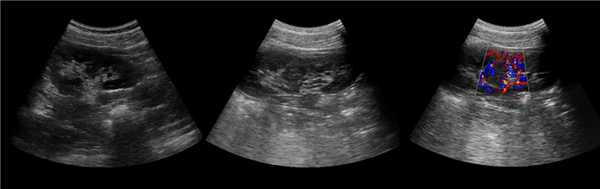

Рисунок. Дистальный отдел мочеточника расширен, в мочевом пузыре анэхогенное образование с тонким и ровным контуром — уретероцеле.

Рисунок. Двустороннее уретероцеле на УЗИ: в режиме ЦДК из верхушек уретероцеле определяется выброс мочи.